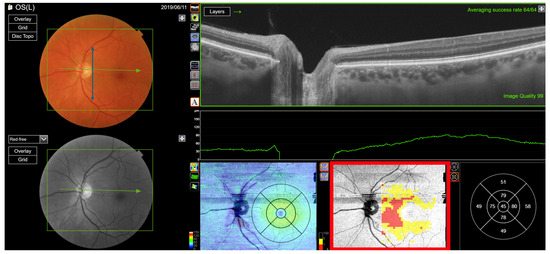

Figure 8. Type 5 RNFL thickness deficit alert from a left eye with a normal visual field. The angle between the temporal nerve fibre ridges is large (B). Thickness deficit alerts, as projected on the visual field, are associated with a nominal thickness deficit at the temporal meridian (B), which is balanced by thick RNFL elsewhere. The alert types are radial defects, centre artefacts, and temporal ripples. The peripapillary retinal nerve fibre layer (RNFL (A)) and its thickness curve in ((B) black, blue and purple); N, nasal; S, superior; T, temporal; I, inferior quadrants; 0 degrees representing the temporal horizontal meridian. Red vertical lines (B) show the location of the superior and inferior arcuate trunk vessels. The peaks of the superior and inferior arcuate nerve fibre ridges or the template or reference curve are close to the innermost red lines. An en face slab of the inner retina shows the RNFL analysis (C), RNFL thickness map (D), and RNFL sector analysis (E). The macular ganglion cell and inner plexiform layer (GC-IPL) thickness map is shown on (F). The RNFL probability map is shown on (G) and the GC-IPL probability map on (H). In (G+H) green colour indicates that thickness is within the best 95% of healthy subjects at a given test location. For other colours, see colour bar next to (G+H). VF, visual field. GCL+ above = GC-IPL.

The Type (5) Radial defects, seen in 144 eyes (23%), typically spans the edge of the macular visual field at a distance of 8 ± 4 degrees from the centre of the visual field (Figure 8). Their location and direction suggest that they may be related to the periodicity of the peripapillary nerve fibre layer thickness curve associated with the intercalation of the RNFL with the peripapillary vessel segments. This phenomenon is hypothetically influenced by the method used to interpolate RNFL thickness, where the layer is interspersed with large vessels. This artefact is most prominent within 8 degrees of the centre of the visual field. Of the 144 eyes, 71 (49% of the eyes in the group and 12% of all the eyes) showed predominantly radial defects, whereas 73 (51% of the eyes in the group and 12% of the total eyes) also displayed other prominent RNFL-based alerts (Figure 8).